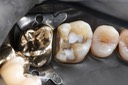

Mark Chun #14 prep